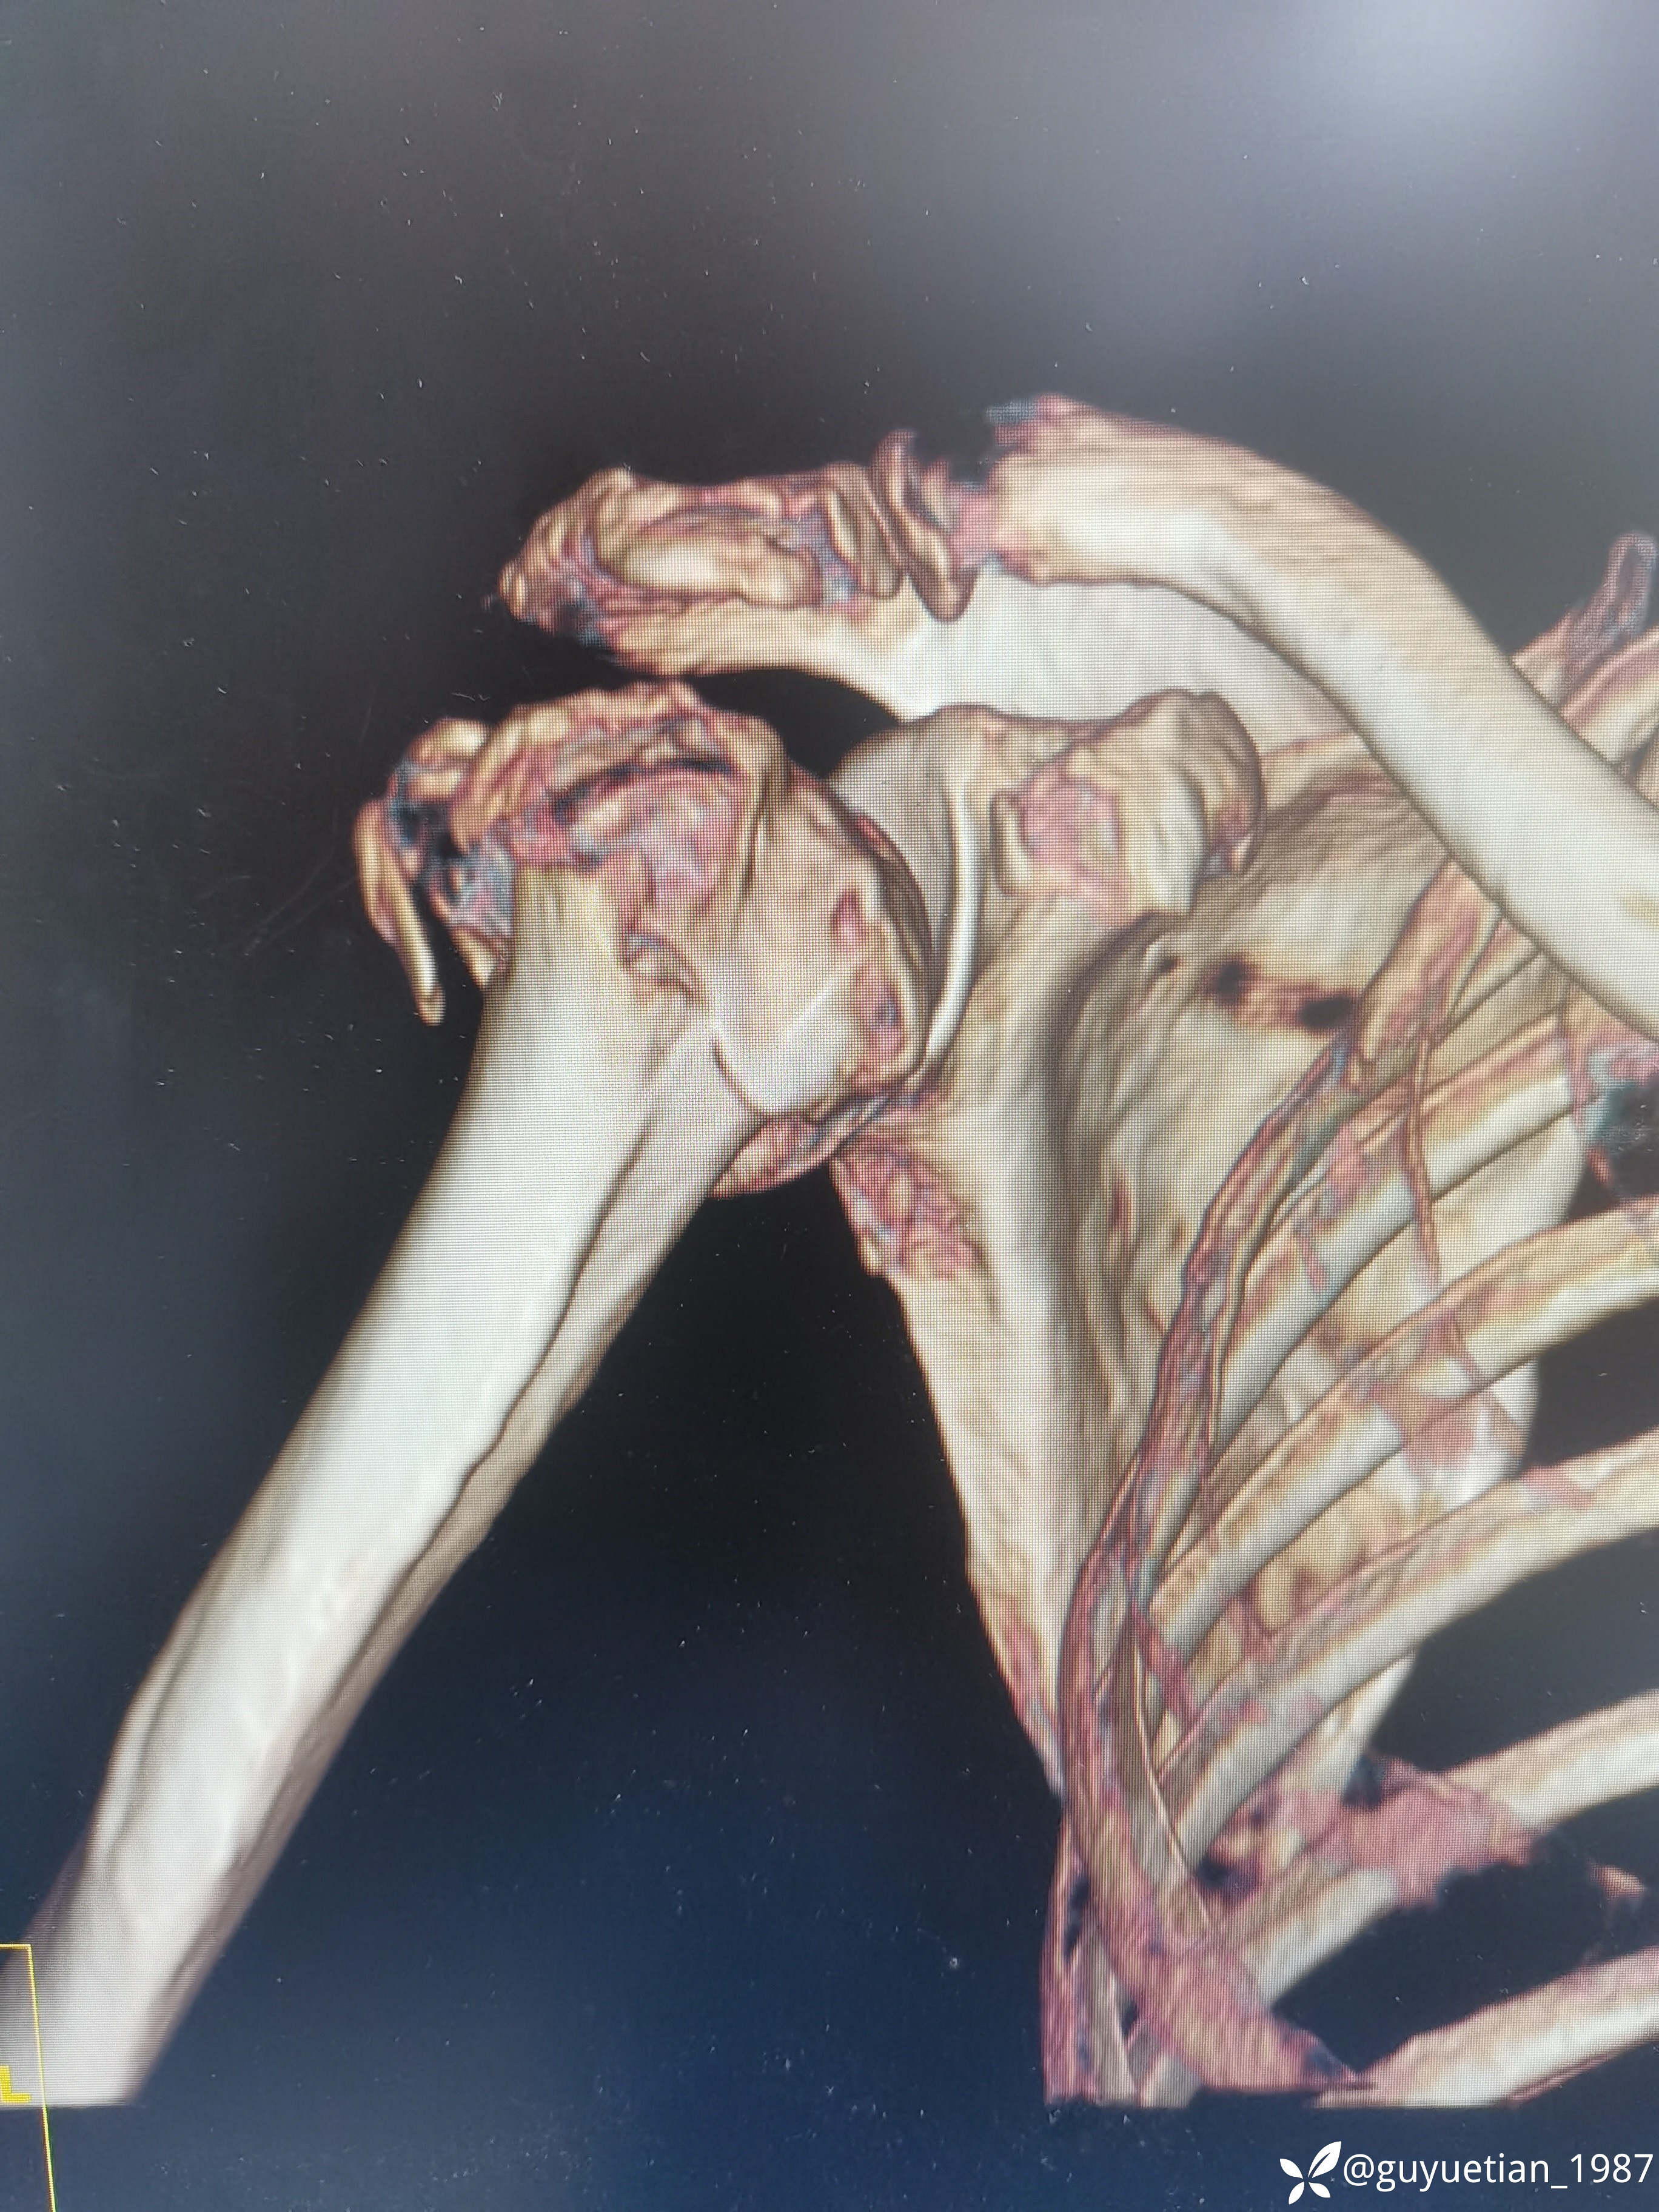

内收型,向前成角

家属沟通后倾向于保守,那就尽力而为